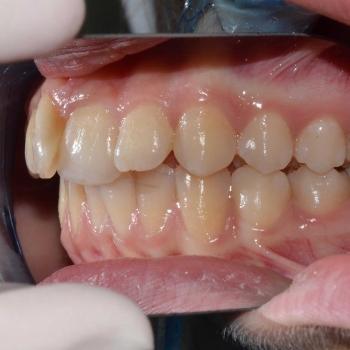

Eszter és édesanyja az iskolai fogorvosuk javaslatára kerestek fel, mert a kolléga, az esztétikai problémát okozó torlódás mellett, Angle II. osztályú funkciós eltérést is tapasztalt. Szerencsére ezeken felül egyéb eltérésre a konzultáció alkalmával sem derült fény.

Eszter a kezelés megkezdésekor headgear típusú fogszabályozó készüléket kapott annak érdekében, hogy a felső nagyőrlőket hátrafelé mozgassuk, illetve, hogy a keletkező rést felhasználjuk a kisőrlők és a szemfogak hátramozdítására is. Az így felszabadult hely az Eszter által választott hagyományos fém fogszabályozó segítségével felhasználható volt a metszőfogak elrendezéséhez, azok túlzott előredőlése nélkül.

A kezelés eredményeként minden kiindulási problémát sikerült megoldani és egy esztétikailag és funkcionálisan is szép mosolyt létrehoznunk.